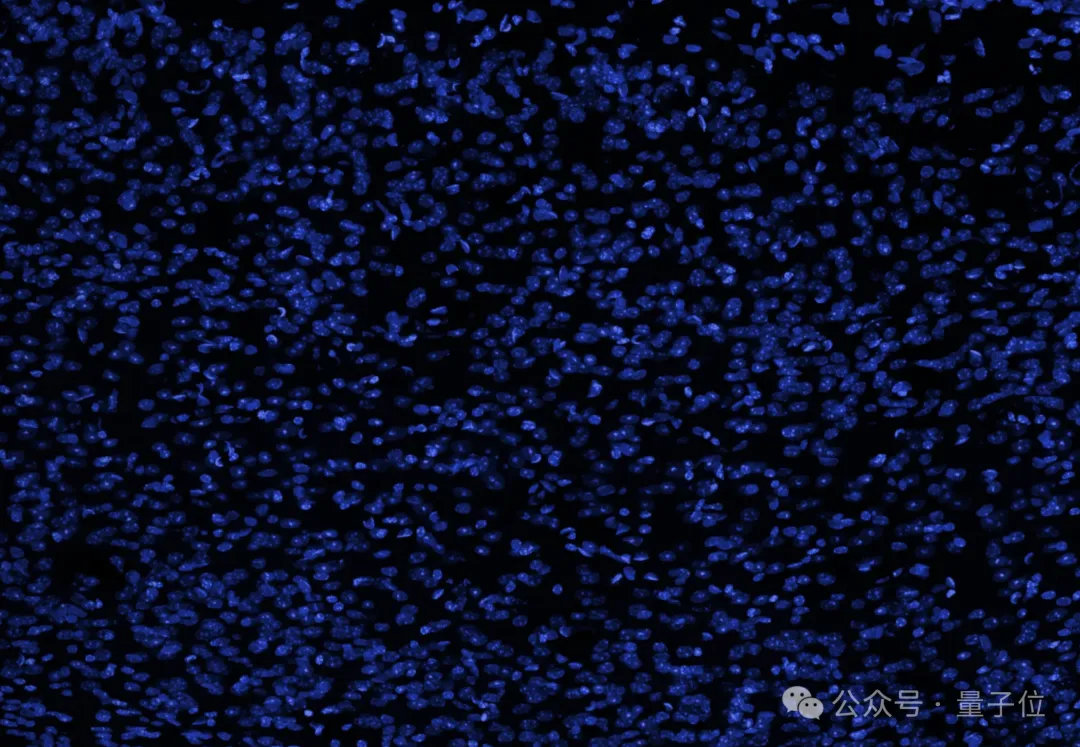

研究团队展示了一张大脑的横截面图像(蓝色表示细胞核),并表示人脑中看似空旷的空间实际上充满了轴突、树突和支持细胞,形成了密集的突触网络。